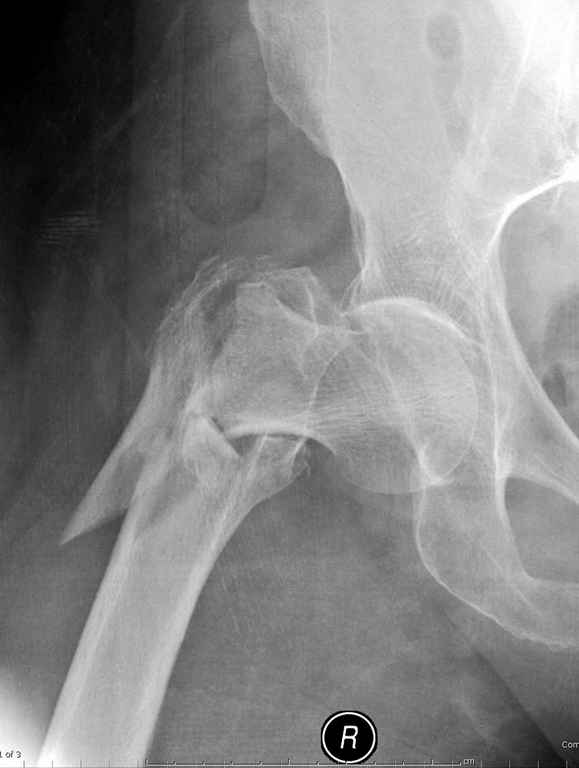

Предугадать распространение линий перелома при чрезвертельных и оскольчатых переломах трудно, поэтому для принятия правильного решения рекомендуется Компьютерно Томографические исследование.

При отсутствии КТ, снимок на вытяжении поможет увидеть общую картину расположения отломков, особенно потенциальные места введения импланта. Риск раскола в этом случае огромный, поэтому больной должен быть дообследован.

Здесь пара похожих случаев.